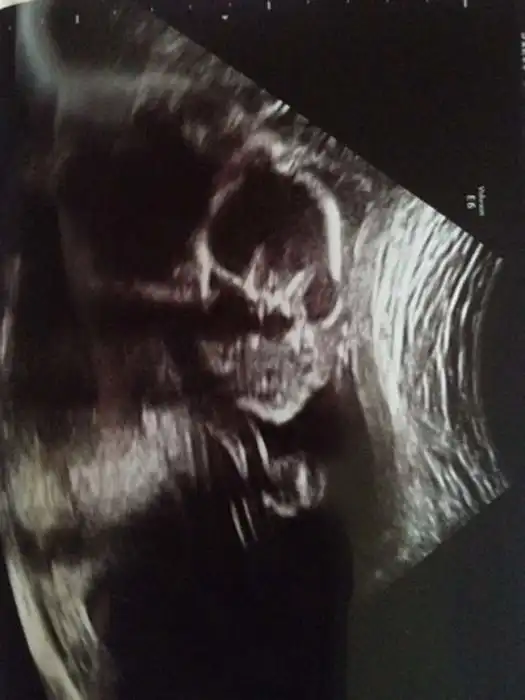

Как выглядят дети в утробе матери на экранах аппаратов УЗИ

На экранах аппаратов УЗИ дети, находящиеся в утробе матери, выглядят далеко не такими милыми и симпатичными, какими они оказываются после своего рождения.